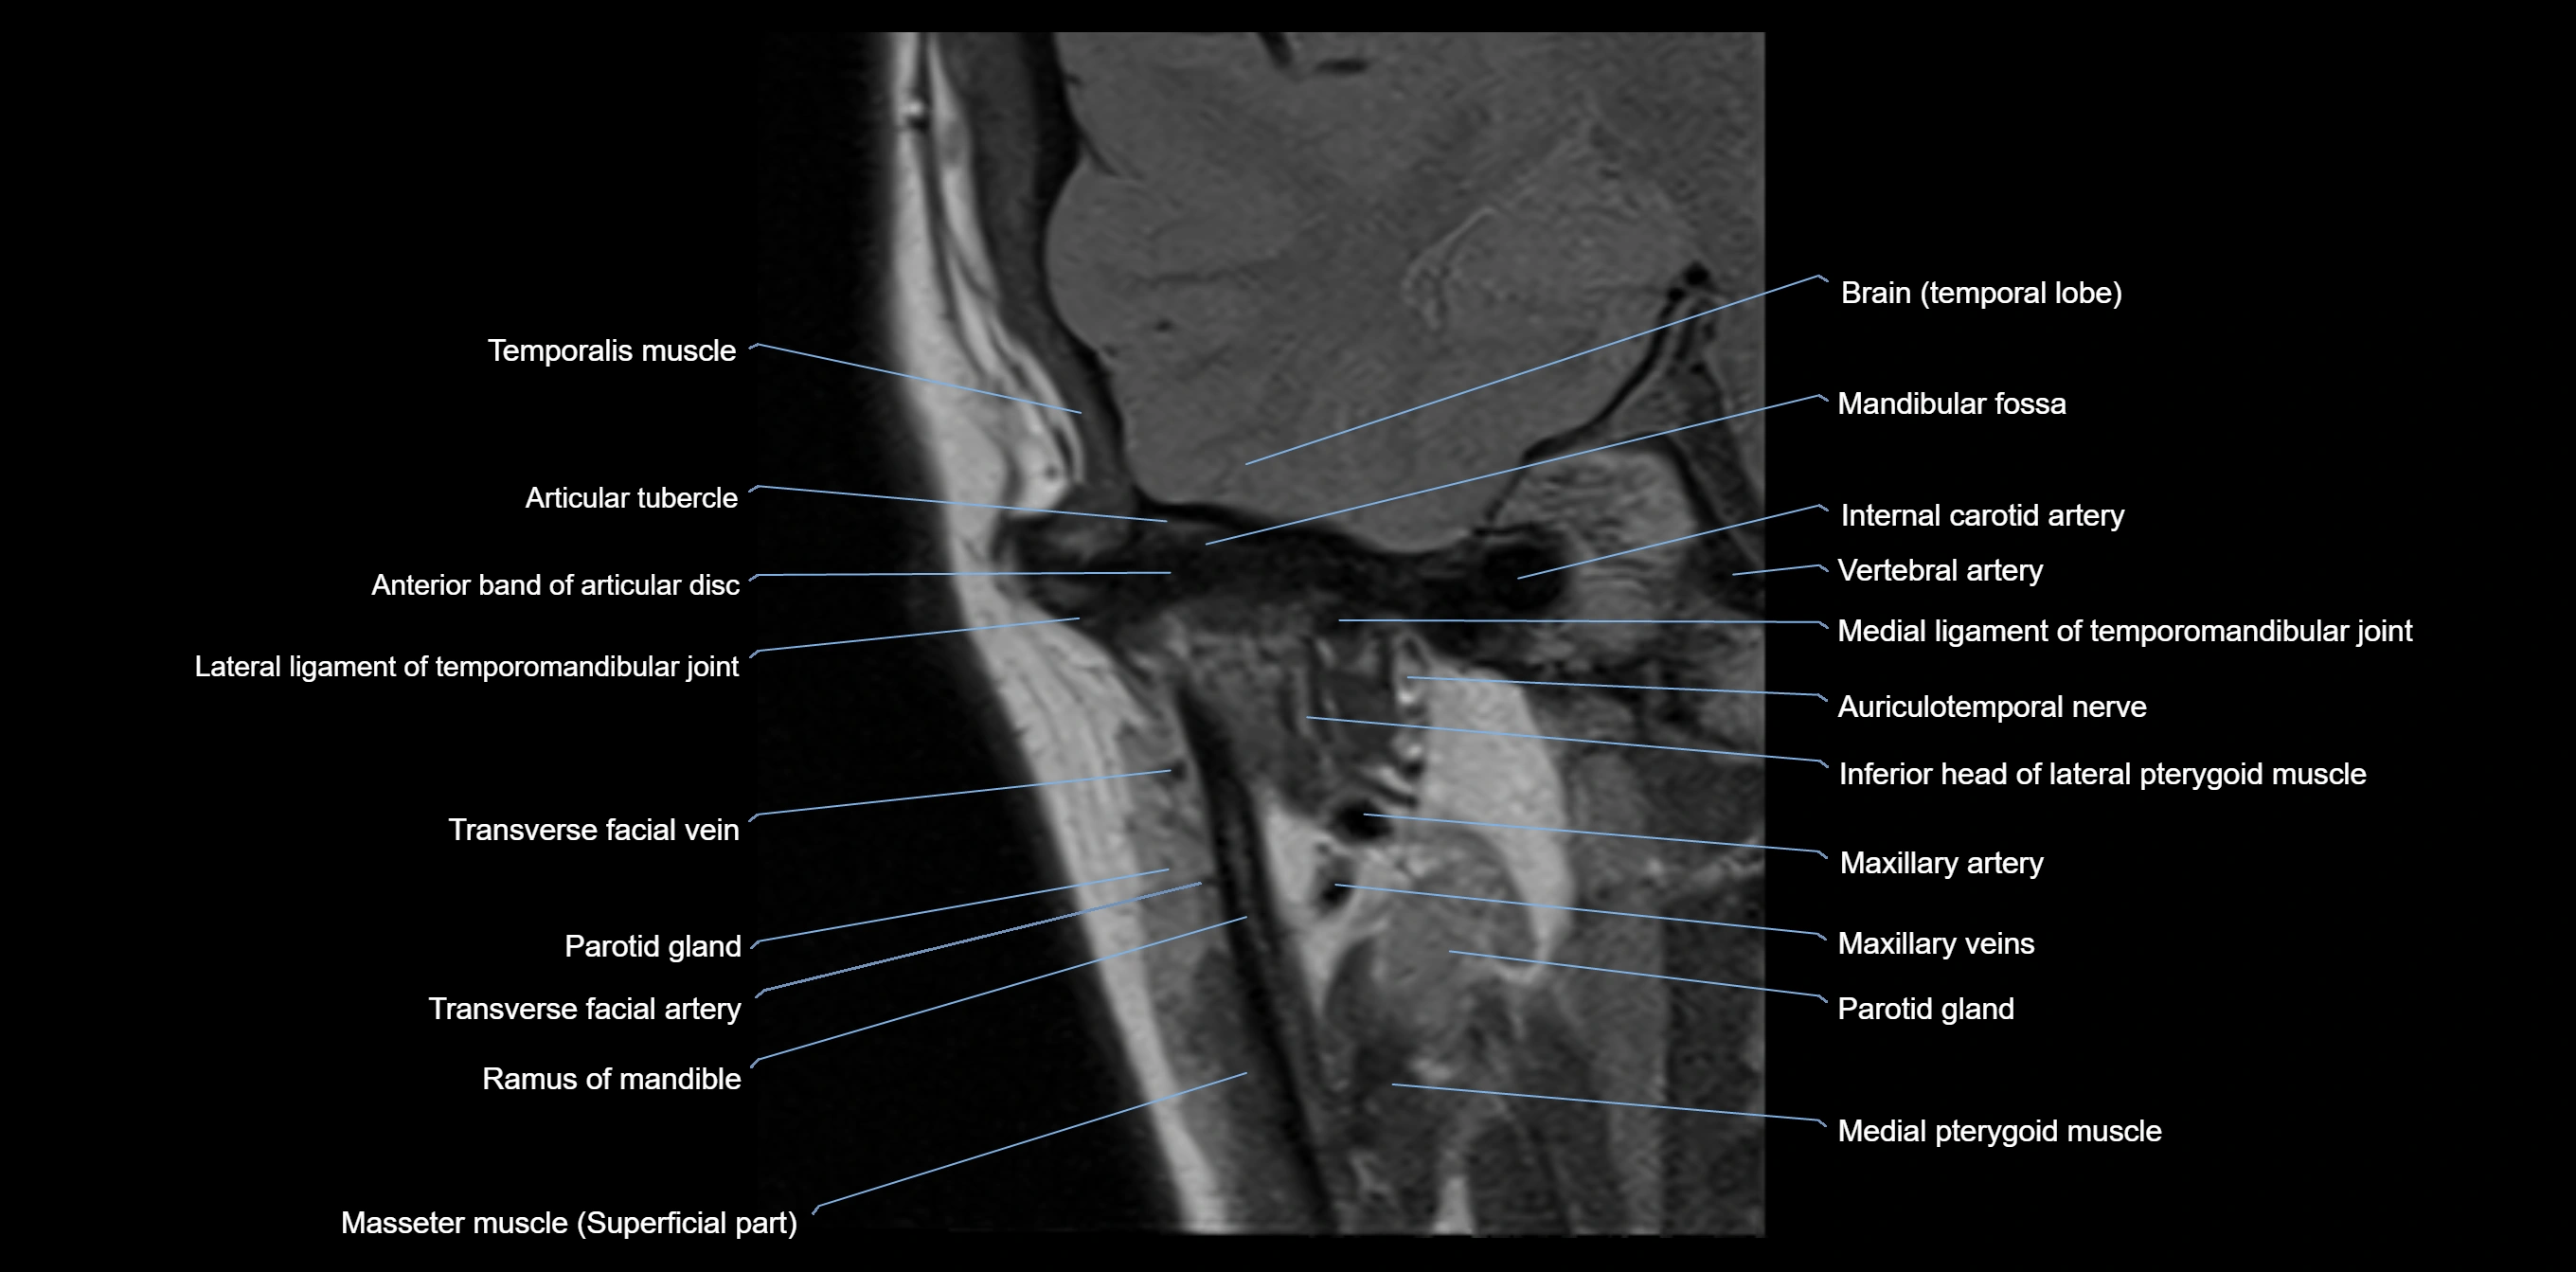

MRI appearance

T1-weighted images:

• Cortical bone: Low signal intensity

• Cancellous marrow: Intermediate to high signal depending on fatty content

• Teeth: Signal void structures

• Adjacent soft tissues: Normal gingiva and oral mucosa signal

T2-weighted images:

• Cortical bone and teeth: Low signal

• Marrow: Intermediate signal